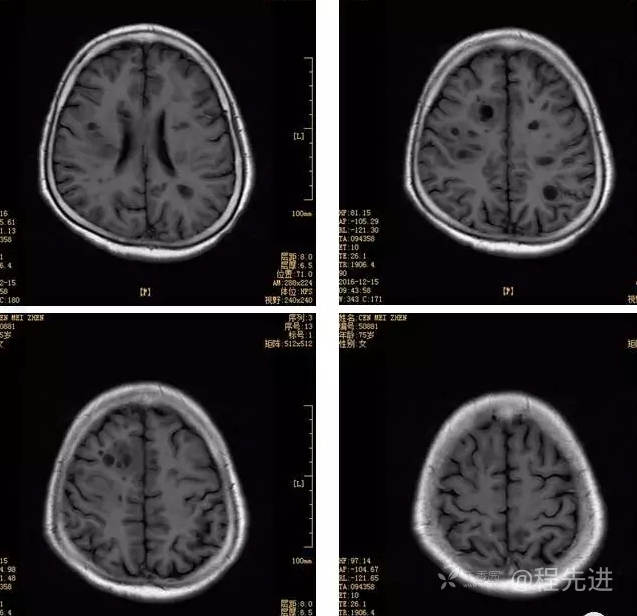

3月特别精彩病例|头晕伴左侧肢体乏力、行走不稳1周【结果已公布】

患者性别:女

患者年龄:75岁

简要病史:头晕伴左侧肢体乏力、行走不稳1周。否认高血压、脑梗塞、肝炎、糖尿病、肺结核病史。否认疫区疫水接触史。